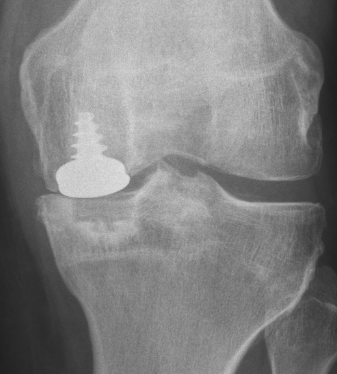

ci-dessus: images radiographiques après l'opération: à gauche, on voit le "patin" femoral de face; à droite, on le voit de profil, et on remarquera la vis en titane qui permet d'ancrer la surface en acier poli dans l'os.

Exemple 2: homme de 45 ans, usure des deux versants de l'articulation.

Radiographies après l'opération: on voit bien le patin femoral; le bouton tibial se distingue moins bien, car il est transparent aux rayons X.